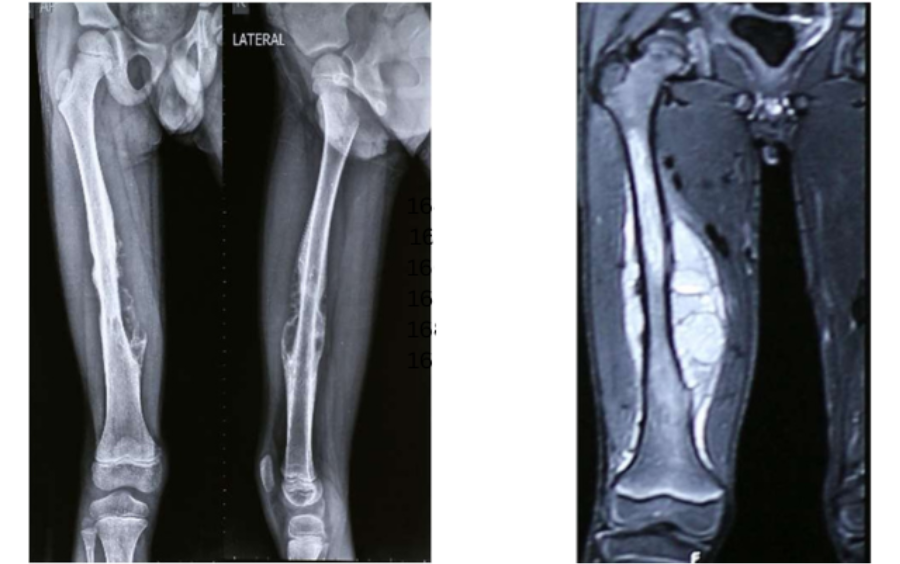

After histopathology, doctor diagnosed with Left side proximal humerus recurrent Chondrosarcoma.

Onco Orthopedic Dr. Pramod Chinder surgeon in Bangalore, decided the surgical plan- Considering the extensive extent and size of lesion, the surgery was divided into two parts performed on two different days: day 1 involved wide resection of the tumor in the left proximal humerus encasing the clavicle and scapula. Along with the tumor mass, upper half of scapula, lateral 2/3rd of clavicle and proximal half of the humerus had to be removed. Day 2- involved shoulder reconstruction with the help of 3D printed humerus, scapula, clavicle, and reverse shoulder arthroplasty implants. Incredible team discussed with Surgeon, the designing and entire manufacturing process. Read more